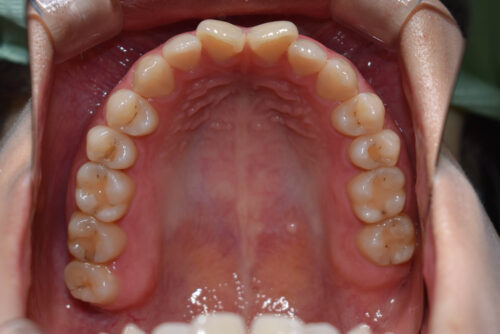

開咬(前歯が噛まない、隙間がある)かみ合わせ変化ワイヤー9か月

初診時年齢28歳女性

歯のがたつき(叢生)と

出っ歯

と

開咬

を気になさり

巣鴨 ・ 池袋よりひとつ隣駅の東京都豊島区大塚駅すぐの大塚たまみ矯正歯科へ

来院されました。

ワイヤー矯正治療9か月後です。